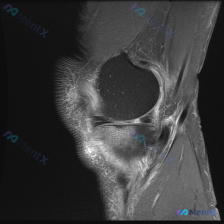

刚看到这个膝关节MRI读片的病例,有点典型,整理出来和大家分享一下思路。 病例基础信息 这是一份膝关节矢状位MRI影像,序列为T2WI或PDWI-FS,对软组织、水肿、韧带病变显示清晰。 影像学核心发现 1. 骨骼与关节软骨:髌骨后方关节软骨面不平整,髌骨软骨下骨可见片状高信号影,提示骨髓水肿或软骨...

刚看到一份膝关节MRI单矢状位切面的读片需求,核心问题是观察半月板异常,我整理了完整的分析思路分享给大家。 一、病例基本影像信息 这是一张膝关节矢状位MRI影像,根据信号特征判断:不符合典型T1加权像(骨髓信号偏低,关节软骨、积液呈高信号),更符合质子密度加权像(PDWI)或T2加权像,这类序列对半...

今天遇到一个很有代表性的情况:用户提供了一张膝关节矢状位MRI,主诉提示「半月板异常」,但我们阅片后发现结果和预期完全不一样,整理出来给大家讨论。 基本影像信息 这是一张膝关节矢状位质子密度或T2加权MRI,图像清晰度良好,信噪比适中,没有明显运动伪影,解剖结构显示清晰,层面大致位于膝关节中部区域。...

病例读片分享:临床怀疑半月板异常,MRI却只看到髌周病变 基本影像信息 提供的影像为膝盖MRI-T2序列矢状位,切面位于膝关节前部髌股关节区域,图像存在一定截断伪影,未显示后交叉韧带及大部分后侧软组织结构。 影像核心发现 整理一下客观观察到的异常: 1. 髌前皮下软组织水肿:髌骨前方及皮下组织层可见...